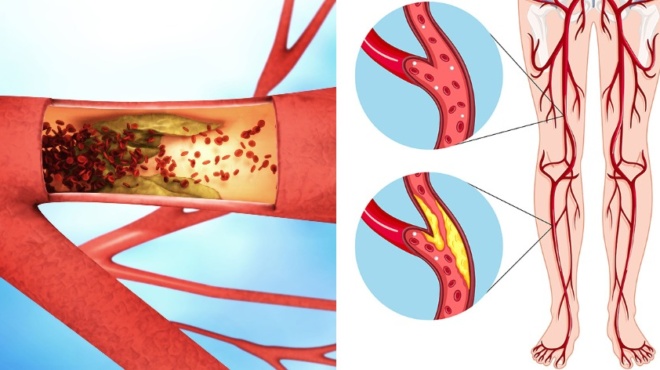

Πόνος στο στήθος: Πρόκειται για πόνο διάρκειας άνω των δέκα λεπτών. Μάλιστα, χρήζει άμεσης διερεύνησης από ιατρό. Ο επίμονος ή οξύς πόνος στο θώρακα μπορεί να σχετίζεται με στεφανιαία νόσο ή πνευμονική εμβολή. Σε κάθε περίπτωση, οφείλεται να καλέσετε τον ιατρό σας. Επίσης, θα πρέπει να μεταφερθείτε έγκαιρα στο νοσοκομείο. Ειδικότερα, αν είστε άνδρας άνω των σαράντα ετών ή γυναίκα άνω των πενήντα ετών.

– Η δυσπεψία ή η γαστροοισοφαγική παλινδρόμηση (το περιεχόμενο του στομάχου ανέρχεται μέχρι τον οισοφάγο) μπορεί να προκαλούν καυτό πόνο στο στήθος. Αυτό το πρόβλημα μπορεί να επιδεινωθεί με το κάπνισμα, το αλκοόλ, τον καφέ, τα λιπαρά τρόφιμα και ορισμένα φάρμακα. Συχνά περνάει γρήγορα με αντιόξινα φάρμακα ή με γάλα.